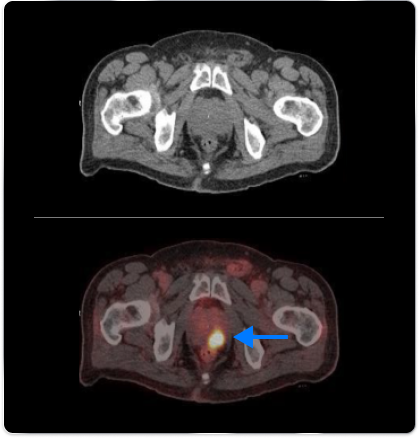

High-risk patient with newly diagnosed prostate cancer

Age

63

PSA (ng/mL)

26

Gleason Score

4 + 3

PYLARIFY may have helped prevent overtreatment